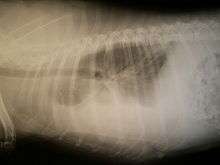

Hemothorax in an animal

A hemothorax (hemo- + thorax) (or haemothorax or haemorrhagic pleural effusion) is a type of pleural effusion in which blood accumulates in the pleural cavity. This excess fluid can interfere with normal breathing by limiting the expansion of the lungs.